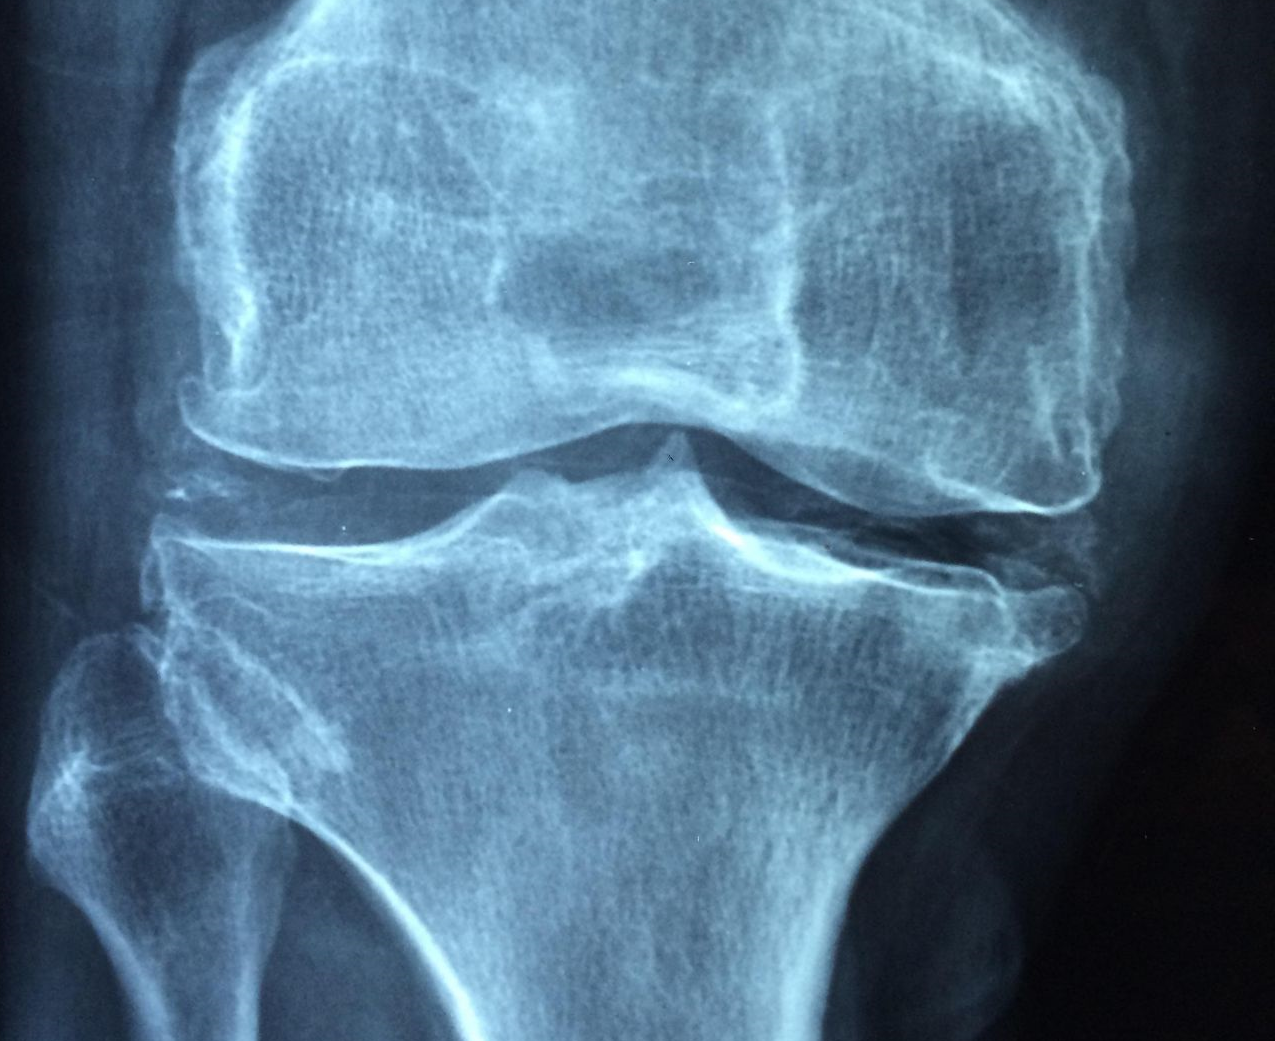

골다공증은 일반적으로 X-선, 혹은 미네랄 밀도 검사(DXA 검사)를 통해 진단됩니다. DXA 검사는 뼈 밀도를 측정하여 골다공증의 정도를 평가하는 데 사용됩니다. 또한 환자의 질병 및 가족력, 통증 여부 등의 정보도 종합적으로 평가됩니다.